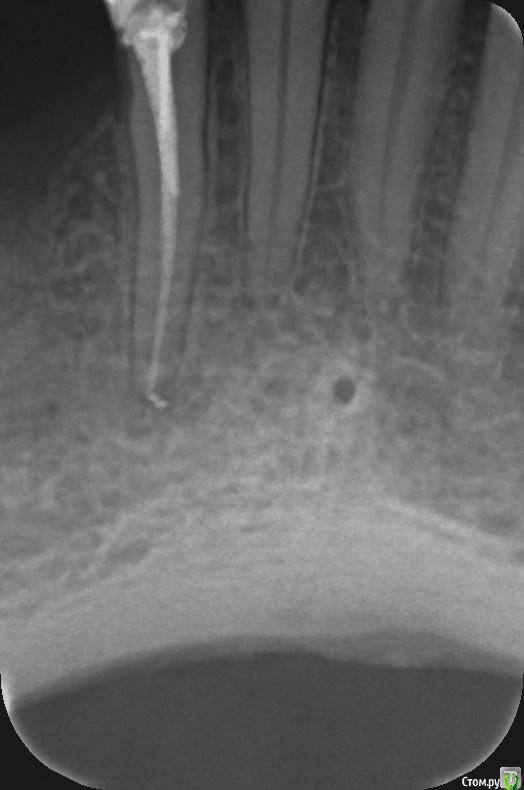

Nata38 Опубликовано 14 января, 2020 Поделиться Опубликовано 14 января, 2020 Здравствуйте, в сентябре месяце лечила кариес нижнего зуба 4.2. Зуб стал реагировать на холодное и горячее. В конце октября депульпировали. Обработка канала была болезненной, хотя ходила с лекарством в канале. После лечения зуб стал чувствительным (при прикосновении языком, губой) и НЫЛ постоянно в покое. Это продолжалось полтора месяца, стоматолог ничего плохого в канале не видела. В итоге канал раскрыли это было в начале декабря, гноя не было канал промыли положили антисептик и закрыли временной пломбой. В этот же вечер боль прошла, зуб остался таким же чувствительным при прикосновении но боли не было. Так я проходила до 26 декабря и зуб мне закрыли заново постоянной пломбой. Вместе с лечением этого зуба мне удаляли зуб на другой стороне сверху под мост, и поэтому с 26 декабря я принимала антибиотики и обезболивающее курсом. А сейчас та же ноющая боль вернулась в мой нижний зуб 4.2. Помогите пожалуйста разобраться, от чего он болит? Снимок есть только после второго перелечивания канала. Ссылка на комментарий

Nata38 Опубликовано 18 января, 2020 Автор Поделиться Опубликовано 18 января, 2020 Спасибо. Сделаю КТ. Врач уверяет, что канал 1. Скажите а пломбировочный материал не выведен за верхушку зуба? Ссылка на комментарий